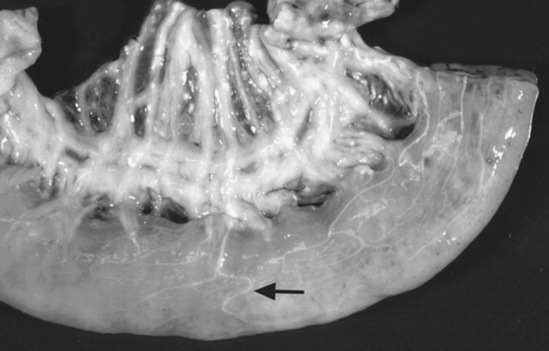

As healing progresses, fibroblasts migrate into the fibrin and a layer of granulation tissue forms both beneath and on top of the original basement membrane (Fig. 32-39). Mesothelial cells produce connective tissue growth factor in response to IL-1β, which simulates fibroblast proliferation.190 During this stage IL-1 stimulates and prostaglandin E2 inhibits fibroblast activity in the injured serosa. Primordial stem cells migrate to the surface and change to form a new mesothelium, a metaplasia likely under the control of growth factor from fibroblasts. The greater the inflammatory reaction within the serosa and on the surface, the more fibroplasia occurs, delaying mesothelium resurfacing and increasing the chance for adhesion formation or bowel scarring. Experimentally the severity of adhesions is correlated with increasing concentrations of TNF-α in peritoneal fluid, and antibodies against TNF-α can decrease adhesion formation.266,267 Healing of the serosa may not result in bowel-to-bowel adhesions but can still cause bowel and mesenteric scarring, which can cause luminal narrowing or kinking. The serosa also becomes thickened, which may result in bowel dysfunction or may interrupt the vascular supply, resulting in chronic obstruction.

Fig. 32-39 Photomicrographs of the serosa with addition of a fibrous layer extending beyond the original level of the basement membrane (arrows) 10 days after bowel ischemia and reperfusion. (Hematoxylin and eosin stain.) The new serosa surface has yet to heal with a new mesothelial layer.